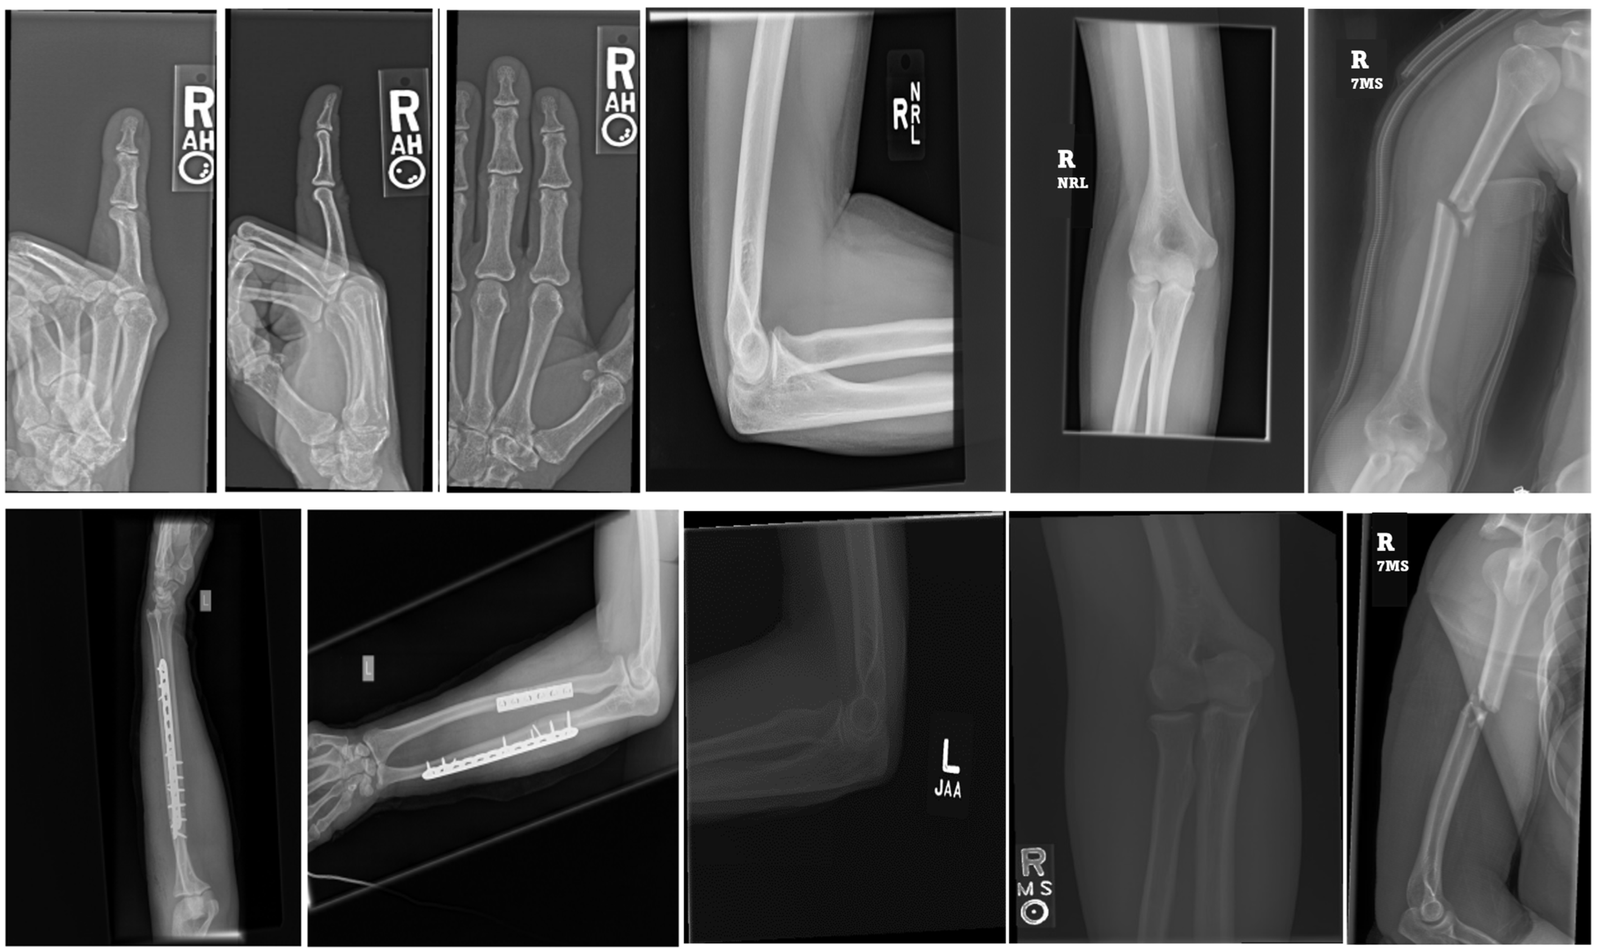

At SOH, we provide effective management ( medical as well as surgical ) of various musculoskeletal disorders like

• - Tennis elbow

• - Golfers elbow

• - Trigger finger

• - De Quervain tenosynovitis

• - Carpal tunnel syndrome

• - Plantar fasciitis